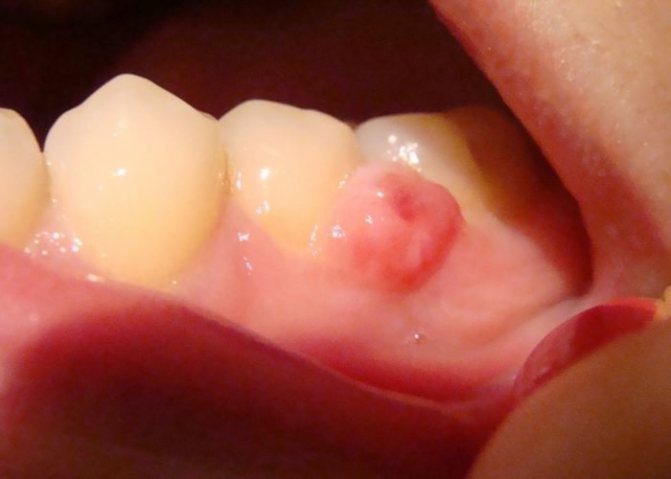

- Папиллома на десне. Такая разновидность обычно не доставляет владельцу неудобств и может быть долгое время незамеченной. Однако нарост может травмироваться во время чистки зубов, что в дальнейшем приведет к негативным последствиям.

Папилломы на деснах

Появление патологических образований в виде шишки или полипа на десне (наросты на дёснах) опасно тем, что слизистая будет травмироваться зубной щёткой или зубными протезами. В конечном итоге это приведёт к воспалительному процессу и инфицированию незаживающих язвочек.

Иногда наросты на дёснах называют фибропапилломой. Несмотря на схожесть в определениях, это новообразование не имеет никакого отношения к вирусу папилломы человека.

Эпулисы. Доброкачественные опухоли полости рта, расположенные на десне. Могут произрастать из глубоких слоев десны, надкостницы, тканей периодонта. Наиболее часто встречаются в области передних зубов. Классифицируются на фиброзные, гигантоклеточные и ангиоматозные образования.